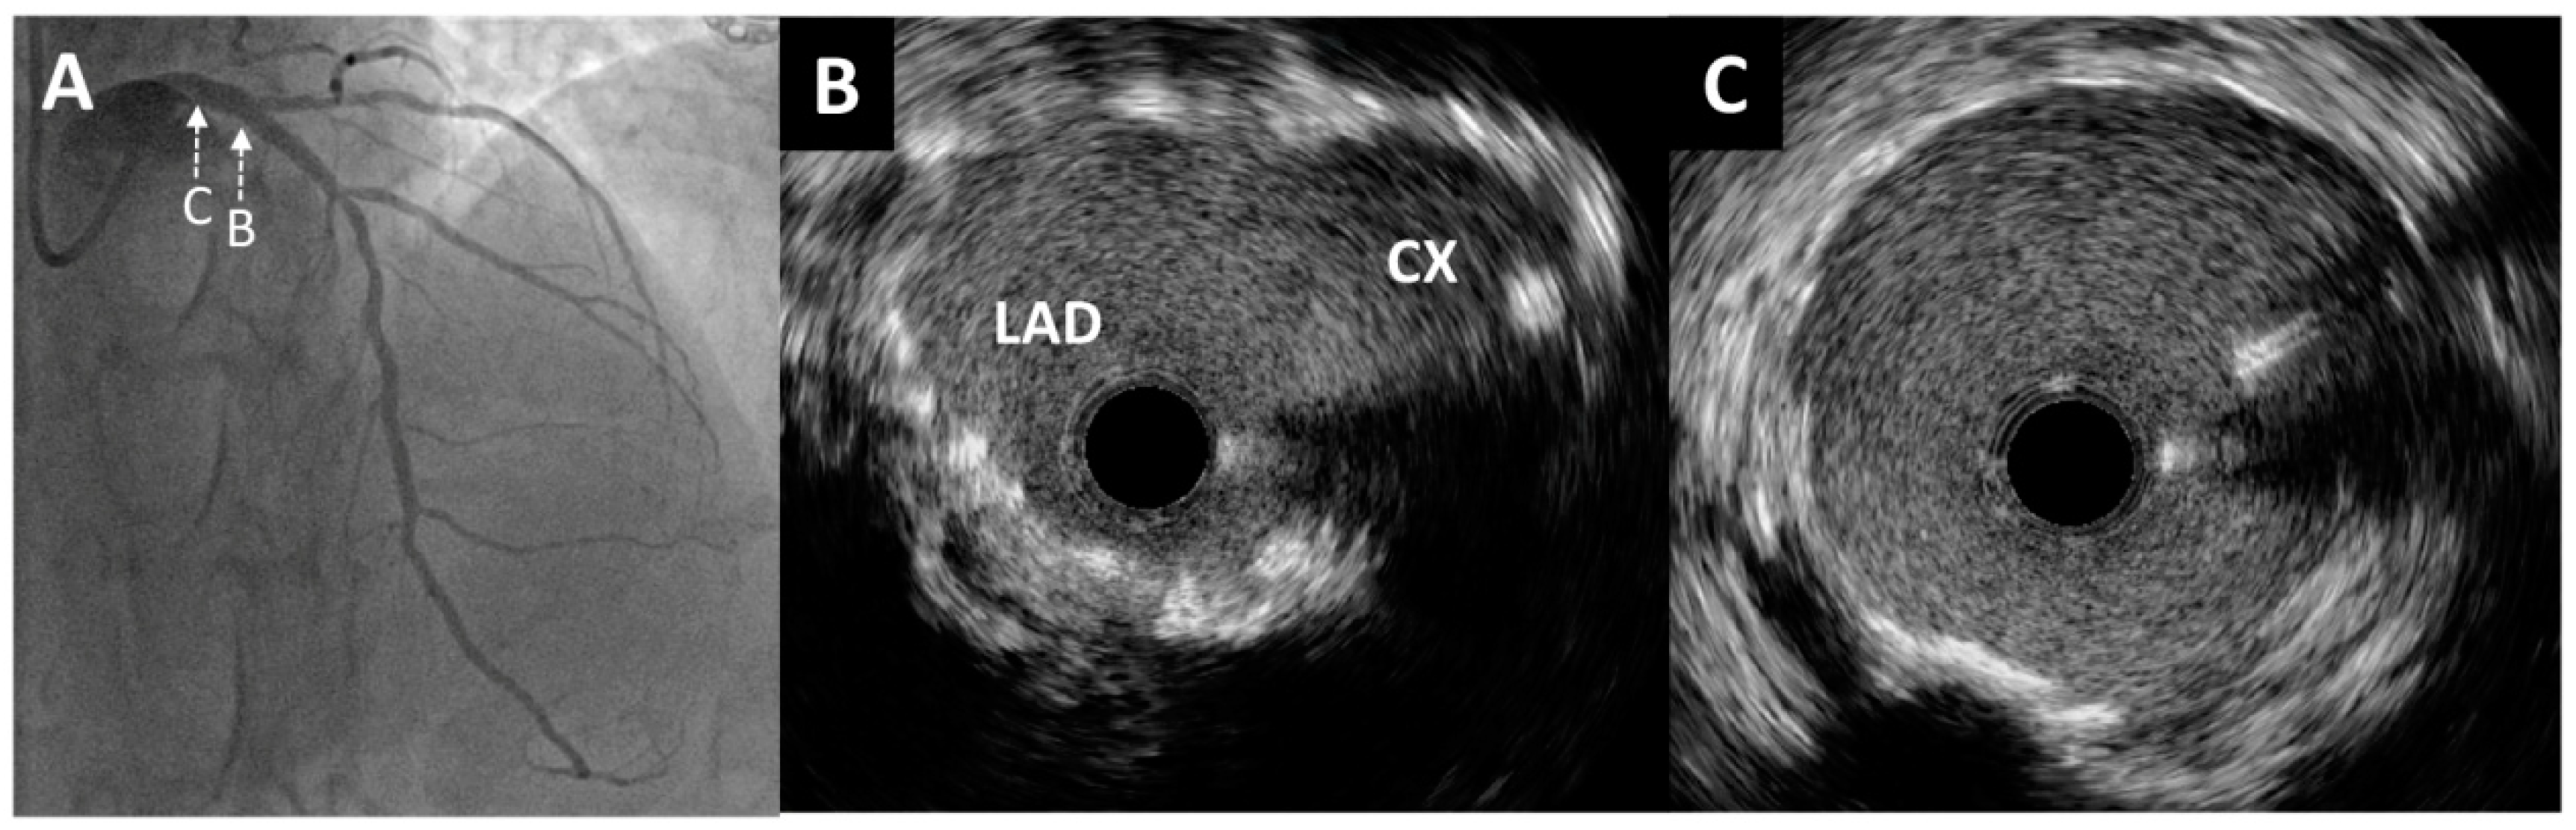

The Role of Intravascular Ultrasound in the Evaluation and Treatment of Free-Floating Stent Struts Following Inadequate Ostial Circumflex Stenting: A Case Report

2. Case Report